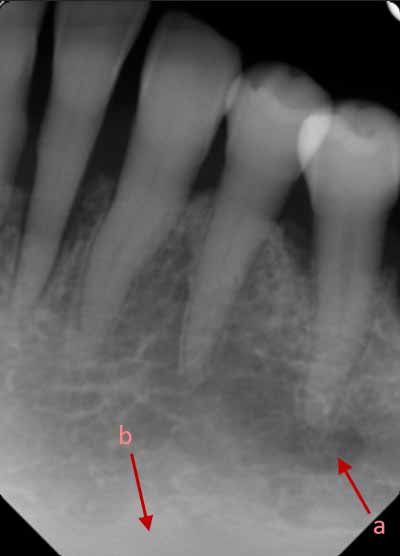

等角投影および平行投影から撮影された適切に配置された口腔内画像では、歯のさまざまな組織とその支持組織を区別できるはずです。歯の周囲では、歯槽突起内の海綿骨と緻密骨の両方を区別できるはずです(画像2を参照)。

X線画像では、被写体コントラスト(X線コントラスト)の違いによって、歯を構成する3つの異なる組織を区別できます。歯冠の外側を覆うエナメル質はミネラル含有量が最も高く、そのためX線写真では最もエックス線不透過性が高いように見えます。象牙質はエナメル質よりもミネラル含有量が少ないため、エックス線不透過性が低くなります。軟組織からなる歯髄は、エックス線透過性の外観を呈します (画像3を参照)。

歯の根の周囲には、繊維性結合組織からなる歯周靭帯があります。これは、根の表面に最も近い薄いエックス線透過性の隙間として描画されます。歯周靭帯に最も近い歯槽骨は、歯槽硬線と呼ばれる薄く緻密な骨組織で構成されています。この緻密骨は、歯の根面に沿って歯槽突起の緻密骨と融合する薄いエックス線不透過領域として描かれます (画像3を参照)。

歯槽骨に、薄くわずかに湾曲したエックス線透過性の線が見えることがあります。これらは栄養管であり、神経と血管のための骨内の小さな空洞です (画像5を参照)。多くの場合、上顎洞の壁でもこれらの栄養経路を識別できます。